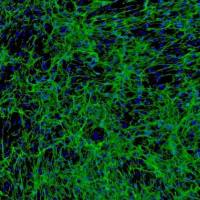

精囊是前列腺附近的一对管状腺,对泌尿系统很重要。在雄性激素的调控下,它们可产生和分泌液体至射精管中。精囊分为三层:内基底黏膜层由单层立方或假复层柱状上皮细胞组成,中间肌层由平滑肌细胞形成,外层由致密结缔组织组成。在精囊中可能出现各种病理条件,包括先天精囊囊肿、精囊炎和一期及二期肿瘤。另外,精囊的侵袭经常作为前列腺癌的预断标志物。精囊上皮细胞提供了一个独特的机会来研究精囊的许多特性。 Sciencell研究实验室的人膀胱微血管内皮细胞是从人膀胱组织中分离提取,属第一代冻存,干冰冰冻运输。每管细胞密度5×10^5/ml。该细胞可通过纤连蛋白的免疫荧光鉴定。本细胞经检测不含HIV-1、HBV、HCV、支原体、细菌、酵母菌和真菌。如采用ScienCell 实验室特制的培养基,可保证此细胞15倍增殖。 推荐培养基:(EpiCM-2, Cat. #4121) 产品使用说明:仅供科研研究使用